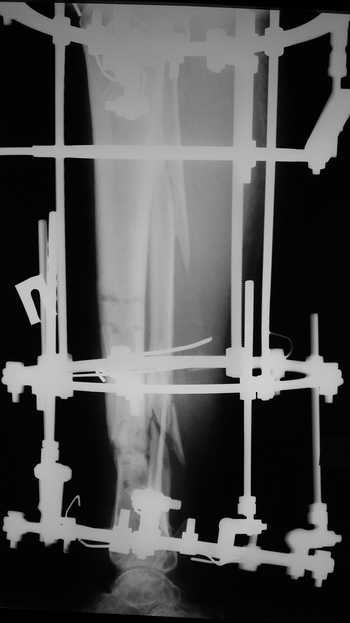

Мужчина, 33 года, резекция б\б кости по поводу остеомиелита после открытого перелома. Стандартная методика билокального остеосинтеза (рис 1 и 2). В конце удлинения выявилось неудовлетворительное взиморасположение перемещенного фрагмента и дистального отломка (рис 3). Планирование (рис 4).

Адаптация отломков гексаподом за 5 дней (рис 5). Замена гексапода на обычные штанги (рис 6 и 7)